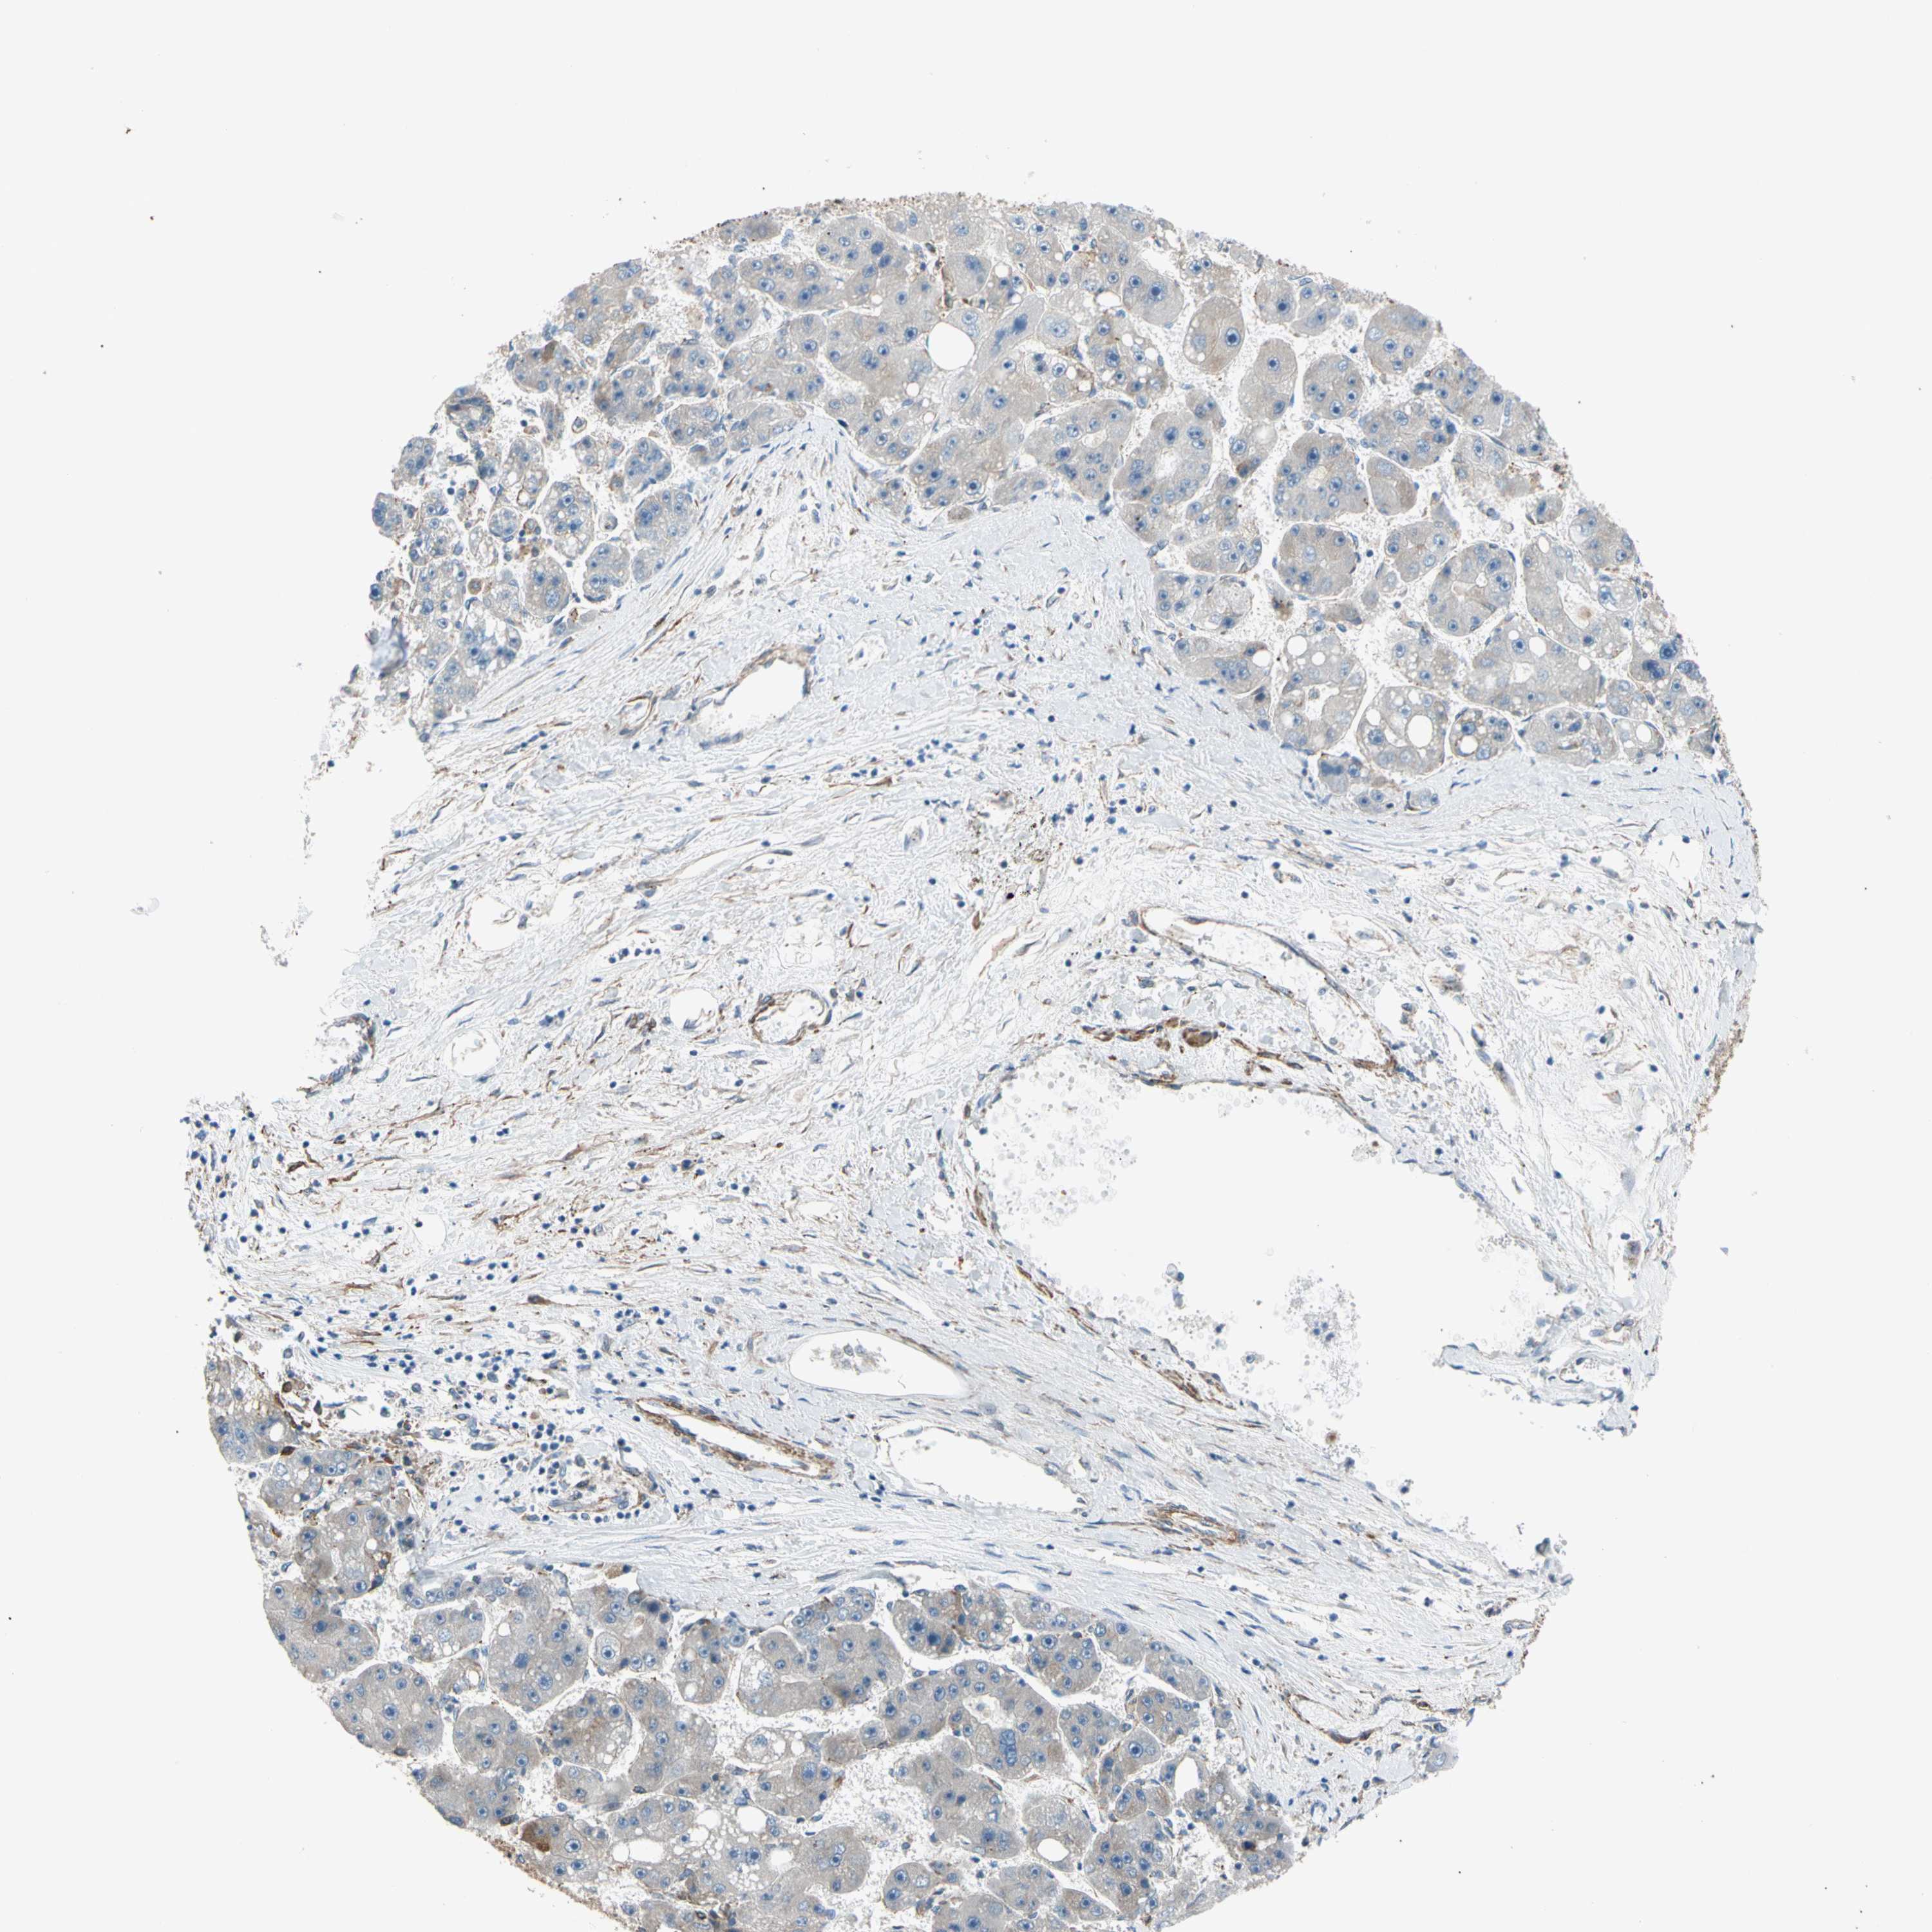

LIVER CANCER - Protein expressioni

A mouse-over function shows sample information and annotation data. Click on an image to view it in a full screen mode. Samples can be filtered based on level of antibody staining by selecting one or several of the following categories: high, medium, low and not detected. The assay and annotation is described here.

Note that samples used for immunohistochemistry by the Human Protein Atlas do not correspond to samples in the TCGA dataset.

Antibody stainingi

Antibody staining in the annotated cell types in the current human tissue is reported as not detected, low, medium, or high, based on conventional immunohistochemistry profiling in selected tissues. This score is based on the combination of the staining intensity and fraction of stained cells.

Each image is clickable and will lead to virtual microscopy that enables deeper exploration of all samples and also displays staining intensity scores, fraction scores and subcellular localization as well as patient and tissue information for each sample.

Antibody HPA008183

Antibody HPA053882

Antibody CAB019313

Staining

High

Medium

Low

Not detected

Intensity

Strong

Moderate

Weak

Negative

Quantity

>75%

75%-25%

<25%

None

Location

Nuclear

Cytoplasmic/membranous

Cytoplasmic/membranous,nuclear

Cholangiocarcinoma

Carcinoma, Hepatocellular, NOS